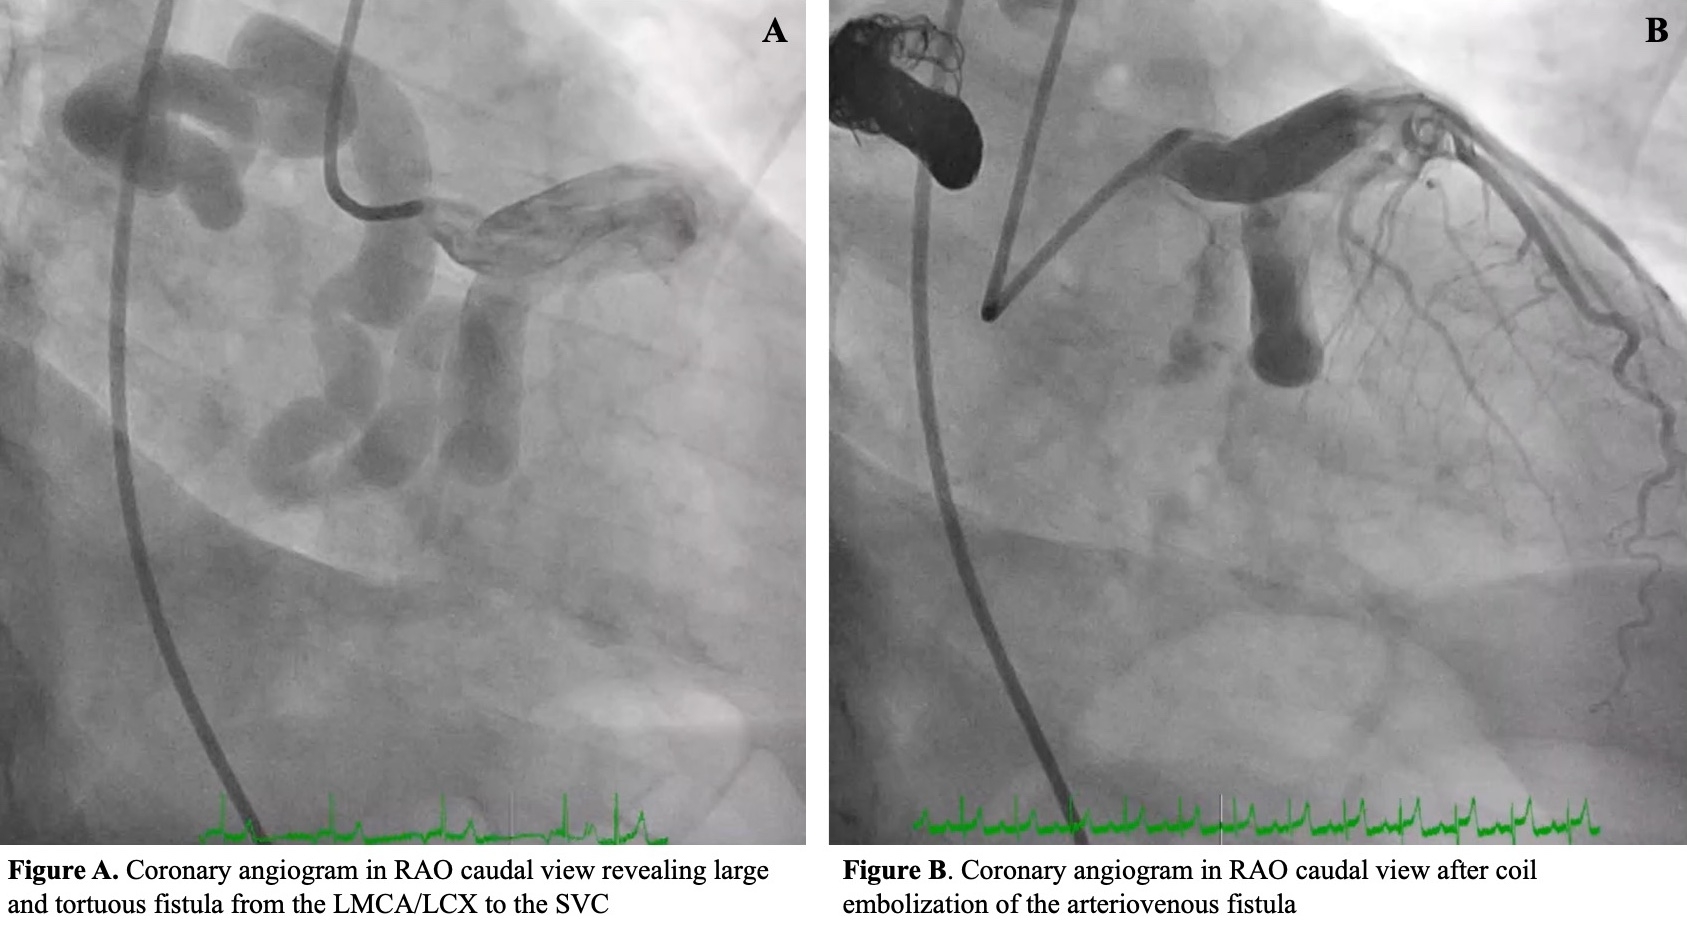

Transcatheter Closure of a Large Left Main Coronary Artery to Superior Vena Cava Fistula Revealed by Symptomatic Tachyarrhythmia

Case Presentation: A 63-year-old male competitive bodybuilder, with no prior cardiac history, presented with lightheadedness and wide complex tachyarrhythmia at a heart rate over 240 beats per minute in the field, requiring two defibrillator shocks. His subsequent EKG demonstrated diffuse ST depressions. Coronary angiography revealed a large tortuous coronary fistula from the LMCA/LCX emptying into the SVC. Transthoracic echocardiogram showed a left ventricular (LV) ejection fraction of 56% and lateral LV wall hypokinesis. Cardiac MRI demonstrated an enlarged right ventricle without delayed myocardial enhancement. Given right sided enlargement and concerns for coronary steal, decision was made to intervene. The patient declined sternotomy to preserve his active lifestyle. Thus, a nonsurgical multi-disciplinary approach was planned for fistula closure. Vascular plug placement was attempted through retrograde venous and antegrade coronary wiring but was unsuccessful due to a narrow and fenestrated single fistula ostium opening and long and tortuous fistula length. From the coronary side, stasis was achieved in the fistula through embolization using 12 microcoils. An electrophysiology study was performed, and the patient’s arrhythmia was consistent with ventricular tachycardia. A subcutaneous implantable defibrillator was inserted for secondary prevention.